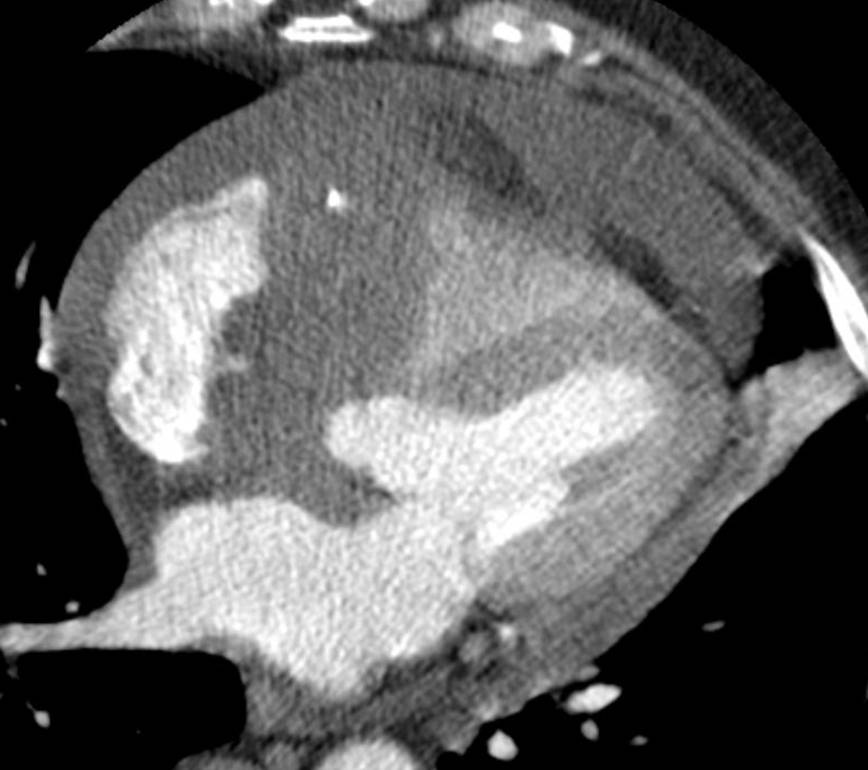

The non-invasive imaging modality of multi-detector computed tomography has dramatically evolved the last ten years and that is due to hardware and software developments. The newer generation of scanners allows increased spatial and temporal resolution that improves the clinical reliability giving further insights into the evaluation of coronary artery disease. Heart morphology imaging followed by studies of myocardial function and assessment of cardiac valves can be performed from the information derived from the data of the coronary artery examination. Also, the venous anatomy of the heart, coronary artery bypass grafts, stents, and cardiac tumors can be imaged and evaluated when necessary. For the beneficial use of this method, entrance criteria for different patient groups need to be set in order to allow improved outcome of multi-detector CT.